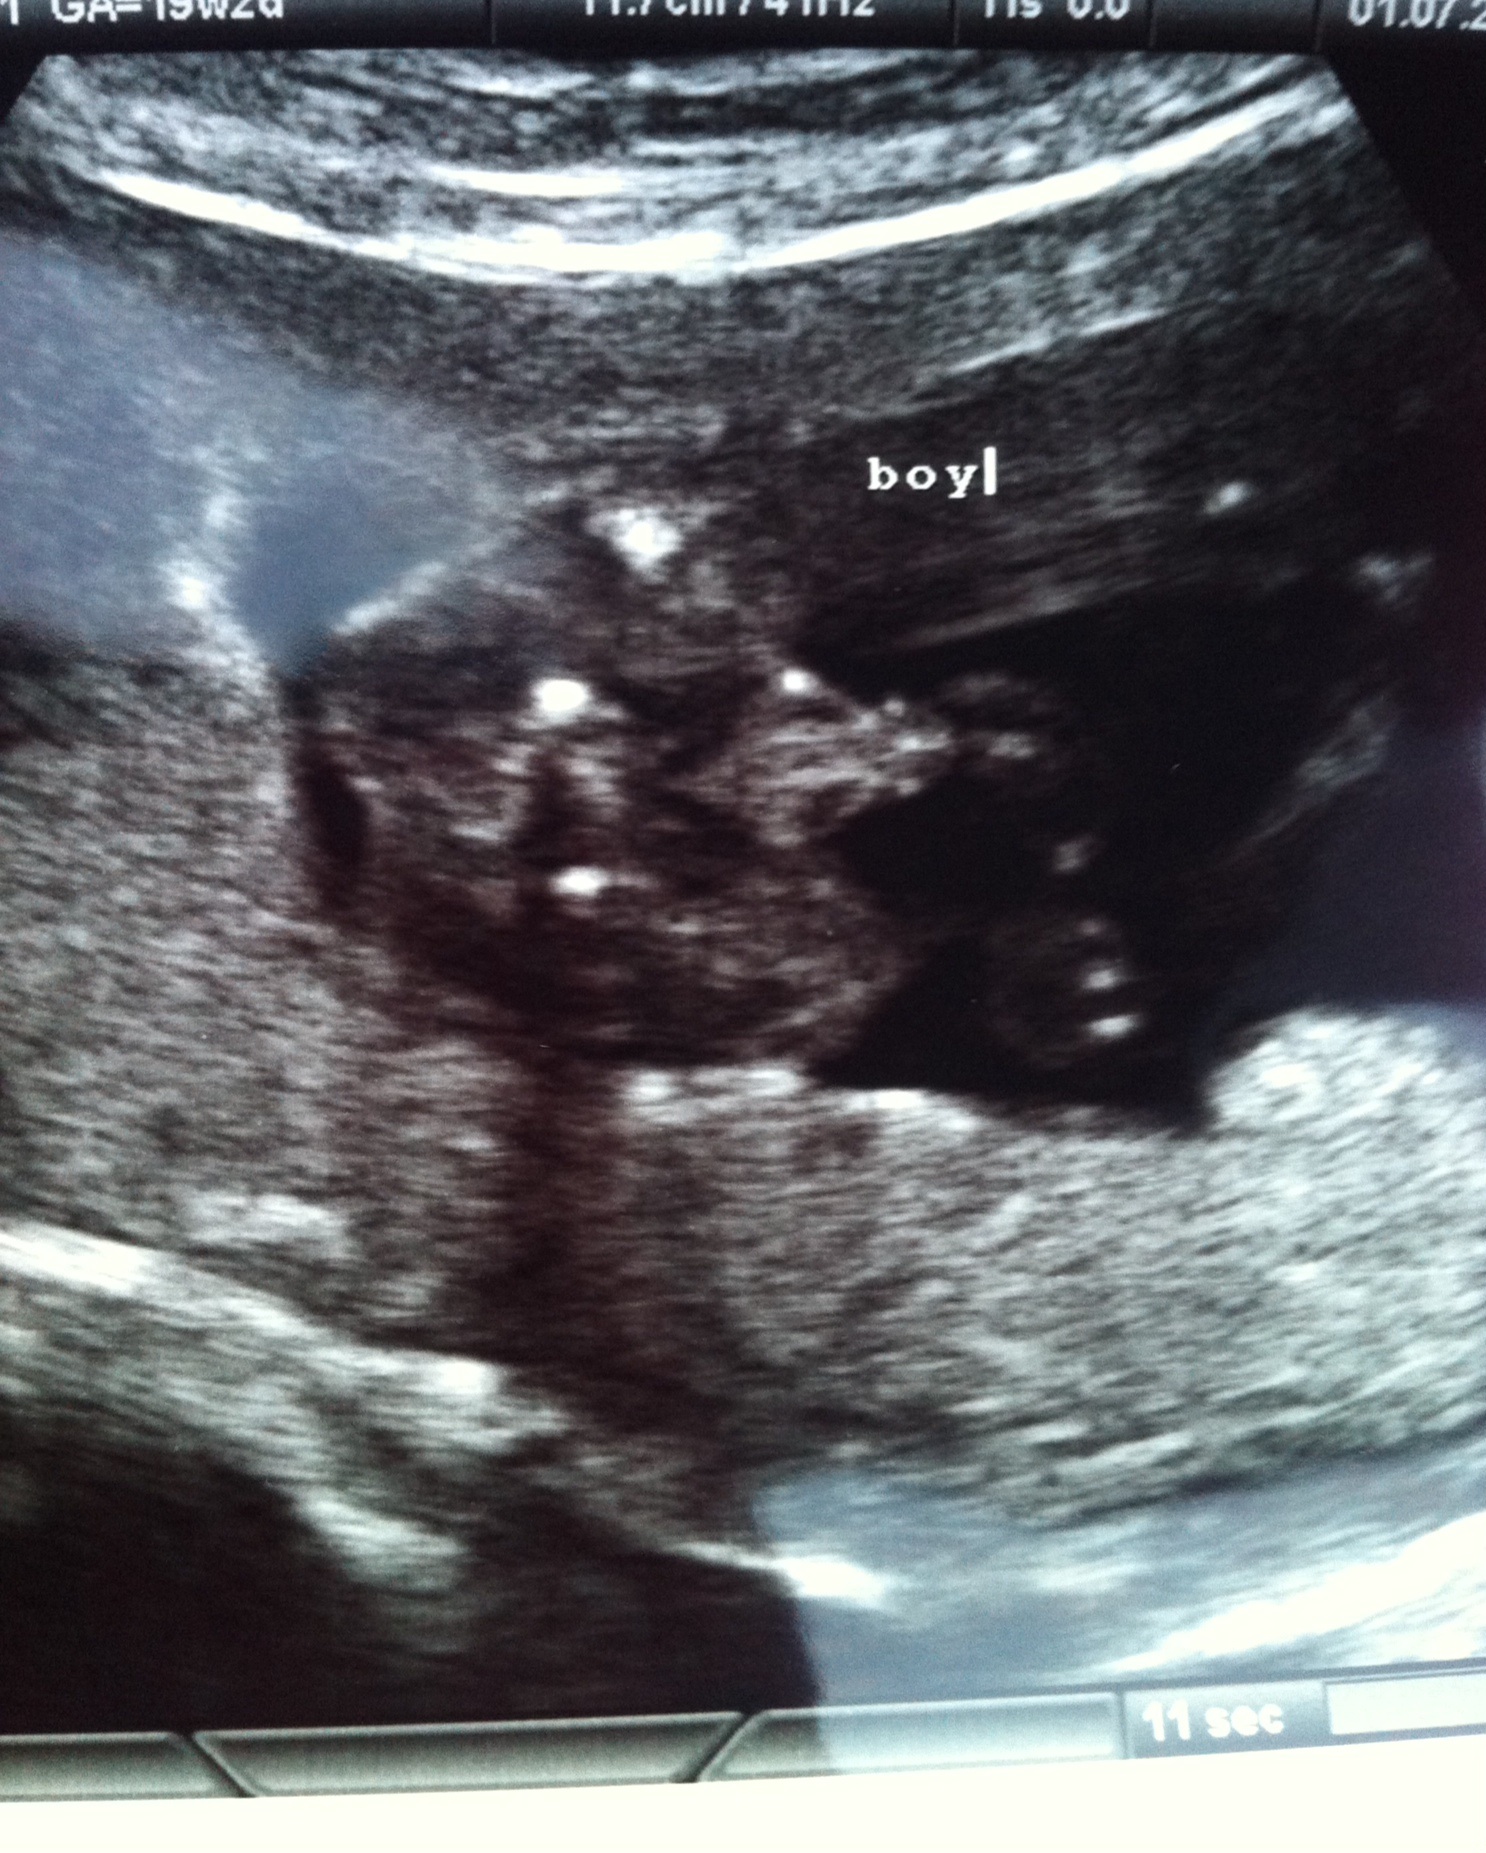

Well here he is my beautiful 3rd baby boy. Decided to get a 3rd scan at a different place , they were brilliant. XxAttachment 19642Attachment 19643